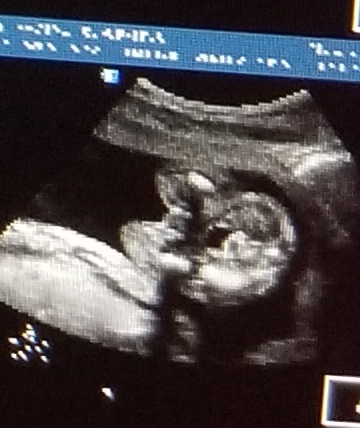

Very blurry potty shot, not sure what im looking at. Any guesses?

Leaning boy but it's really not a clear potty shot. What gestation is this?

This is 19 weeks!

I'm leaning towards boy because of the point, but it's hard to tell for sure.